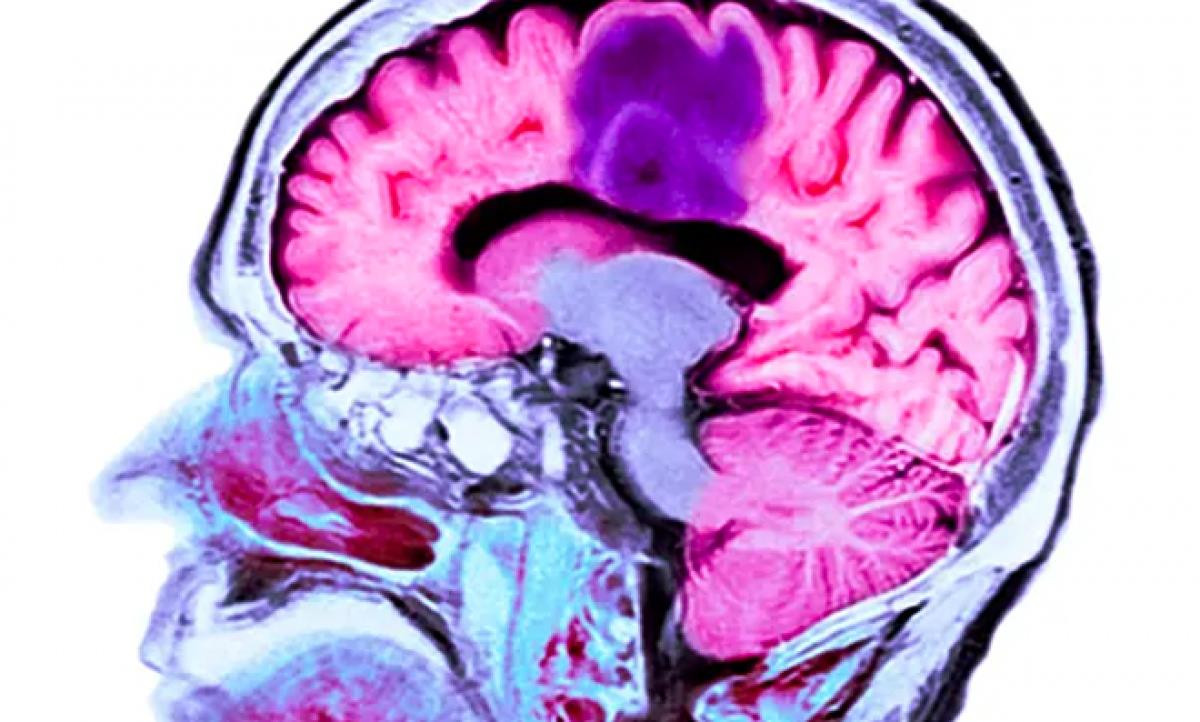

Trong nghiên cứu trên, loại vaccine tên gọi DCVax, dành cho người mắc u nguyên bào thần kinh đệm, dạng ung thư não phổ biến và ác tính nhất. Thông thường, người bệnh chỉ sống trung bình 12 đến 18 tháng sau chẩn đoán, một số thậm chí ít hơn. Tuy nhiên, sau khi thử nghiệm vaccine, một số tình nguyện viên đã sống sót sau hơn 8 năm.

Loại vaccine tên gọi DCVax, dành cho người mắc u nguyên bào thần kinh đệm, dạng ung thư não phổ biến và ác tính nhất.